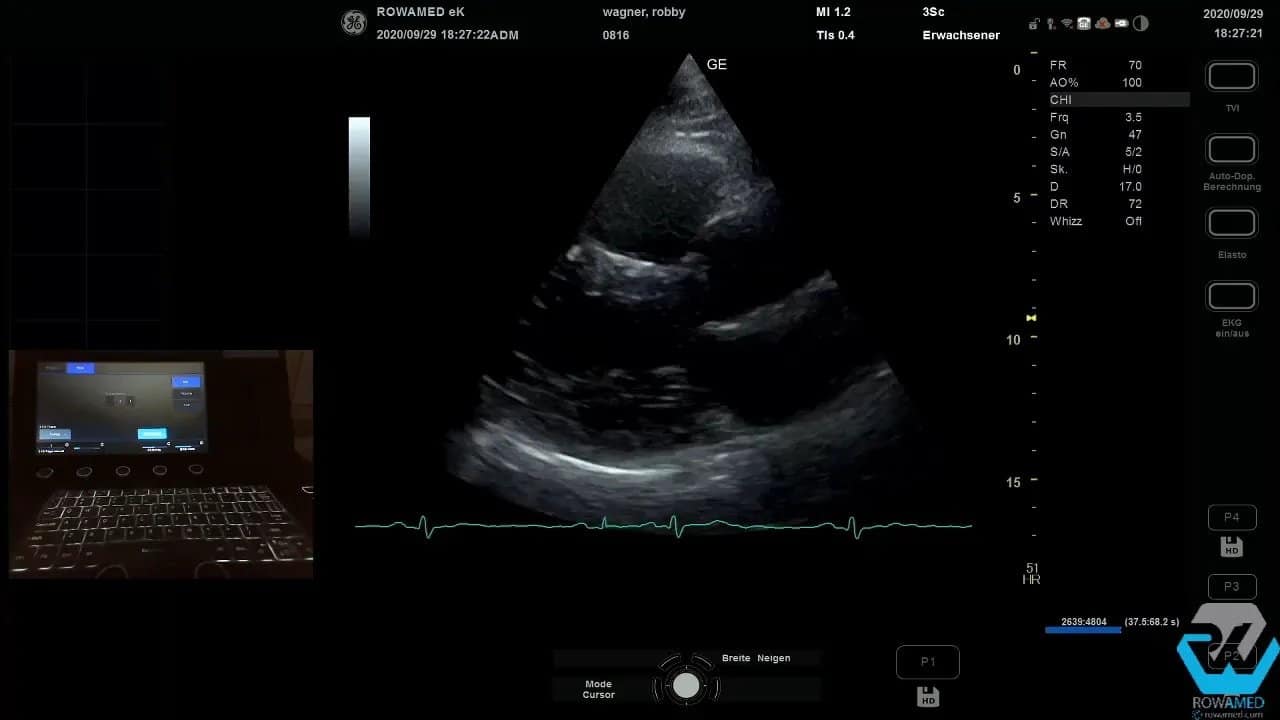

Step 2: Mit der parasternalen langen Achse beginnen

Die Standarduntersuchung startet klassisch parasternal. Die parasternal lange Achse ist häufig die erste und wichtigste Orientierungsebene der Transthorakale Echokardiographie. Hier sehen Sie den linken Ventrikel im Längsschnitt, die Mitralklappe, die Aortenklappe sowie den proximalen Abschnitt der Aorta ascendens.

Diese Ebene liefert schon zu Beginn eine Menge Informationen:

- Größe des linken Ventrikels

- Septumdicke

- globale linksventrikuläre Kinetik

- Morphologie von Mitral- und Aortenklappe

- erster Eindruck zu Regurgitationen im Farbdoppler

In der Enddiastole werden hier die klassischen linearen Messungen durchgeführt. Dazu gehören insbesondere das interventrikuläre Septum und der linksventrikuläre Innendurchmesser. In dem gezeigten Beispiel war das Septum mit 1,2 cm leicht verbreitert, der linksventrikuläre Durchmesser mit 56 mm aber noch im Normbereich. Wichtig ist dabei immer die Einordnung zur Körperoberfläche. Große Menschen haben größere Herzen. Deshalb sollten Sie Grenzwerte nie mechanisch, sondern immer im klinischen Kontext lesen.

Das ist ein typischer Punkt in der Transthorakale Echokardiographie: Zahlen sind wichtig, aber ohne Relation zur Patientenkonstitution oft nur die halbe Wahrheit.